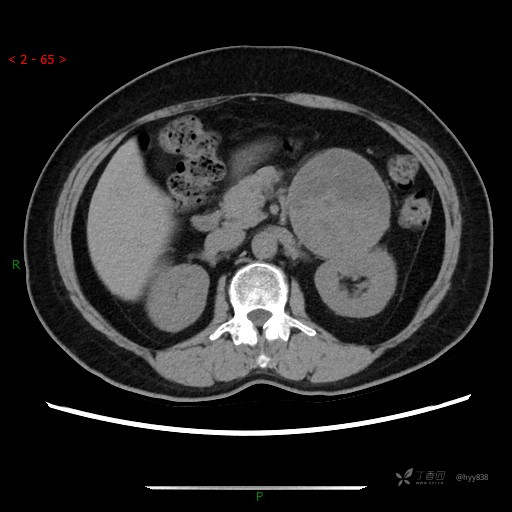

增强静脉期